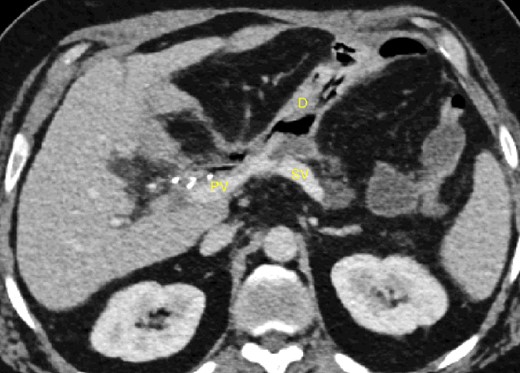

The abdominal exploration was difficult due to significant inflammatory adhesions, which can be attributed to the presence of a pancreatic fistula and the delay of relaparotomy. There was no bleeding observed within the abdominal cavity, and no bleeding was seen from the multitubular drain during the exploration. We hypothesized that the bleeding was of venous origin caused by drain-induced recurrent erosion of peripancreatic vessels, resulting in intermittent bleeding, and that removing drains could help in attaining venous hemostasis. As a result, it was decided to remove the drains. However, this resulted in a significant hemorrhage via the drain orifice. Due to failure to identify the exact origin of bleeding and without the possibility of completion pancreatectomy, we performed a damage control procedure by packing through the drain orifice. This successfully stopped the bleeding. A postoperative CT scan located the packing sponges anterior to the spleno-mesenteric confluence (SMC) (Fig. 2). A percutaneous transhepatic portography showed an irregular aspect of the SMC, without thrombi or contrast extravasation (Fig. 3). After consulting with the interventional radiology team, we placed a cover stent (Fluency™ Bard, Murray Hill, USA) in the SMC (Fig. 4). Two days later, we removed the packs, and a massive hemorrhage recurred, necessitating a new packing. The stent was not seen on a subsequent CT scan. We then performed an endovascular procedure to exclude the segment of the irregular SMC. An Amplatzer™ vascular plug (Abbott Vascular, Santa Clara, USA) was placed in the splenic vein, extending distally to just surpass the inferior mesenteric vein (IMV) insertion (Fig. 5). A cover stent was subsequently deployed in the portal vein, extending distally to the superior mesenteric vein. This allowed for the exclusion of the splenic vein segment that lies between the inferior mesenteric vein insertion point and the spleno-mesenteric confluence (Fig. 5). The packing sponges were removed 10 days later without bleeding recurrence, and the patient finally showed clinical improvement. After 3 years, the stent was visible and permeable on a follow-up CT scan. The scan showed development of venous collaterals, which drain the distal splenic vein and inferior mesenteric vein through the lesser omentum (Fig. 6).

CT scan after relaparotomy located the packs used for hemorrhage control anterior to the confluence of the portal vein and splenic vein. PV portal vein, SV splenic vein.